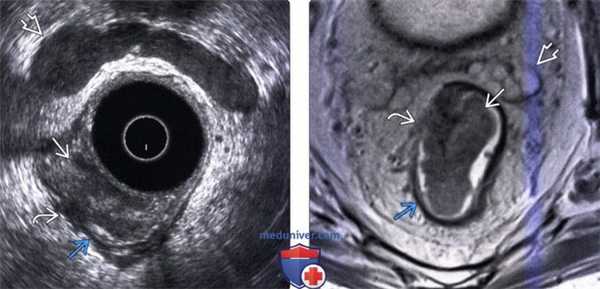

(Левый) При трансректальном УЗИ определяется крупная полипоидная опухоль с экстрамуральным компонентом, прорастающим сквозь гипоэхогенную мышечную оболочку, что определяет стадию. Видны семенные пузырьки.

(Правый) У этого же пациента при Т2 МРТ определяется средней интенсивности полипоидная опухоль с экстрамуральным отростком, тянущимся за пределы низкоинтенсивной мышечной оболочки в мезоректальную клетчатку, что определяет стадию. Визуализируются семенные пузырьки.